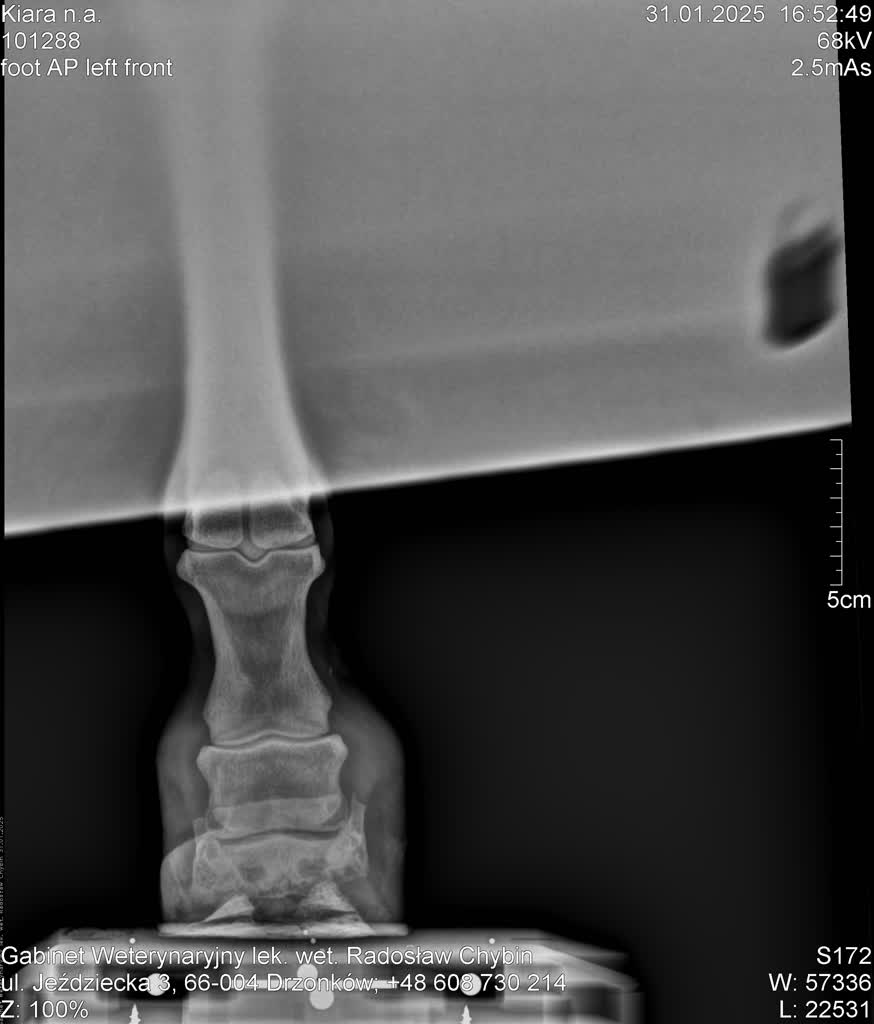

W nowym miejscu Kiara natychmiast otrzymała świeże siano, a opiekunowie okazali jej troskę i zapewniali, że jej sytuacja ulegnie poprawie. Lekarz weterynarii, który dokładnie zbadał stan klaczy, ze szczególnym uwzględnieniem jej zdeformowanych kopyt wskazał na konieczność konsultacji z kowalem oraz wykonania badań diagnostycznych, takich jak zdjęcia rentgenowskie. Podkreślił również, że proces przywracania Kiarze swobody ruchu i eliminacji bólu będzie wymagał czasu i starannej opieki.